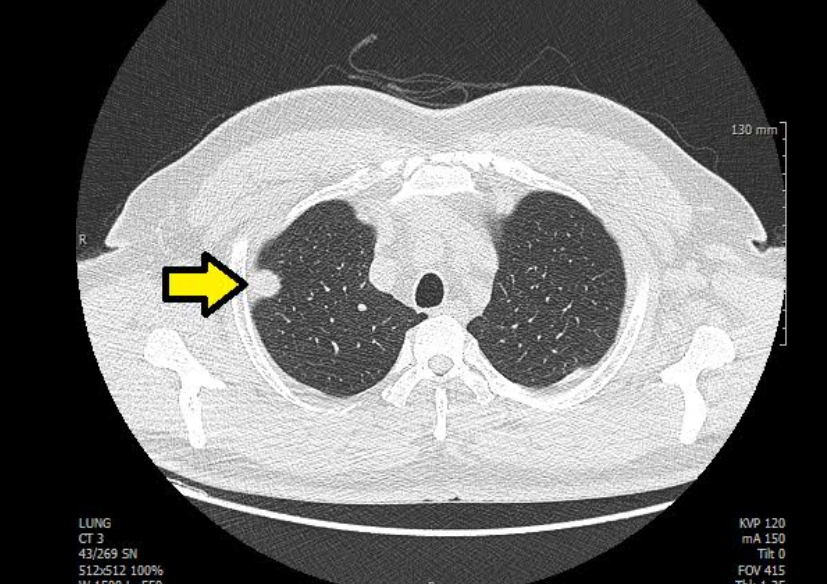

폐 편평세포암은 폐암의 한 유형으로, 주로 흡연과 관련이 있습니다. 기침이 3주 이상 지속되거나 피 섞인 가래, 숨이 차는 증상이 있으면 검사를 받아야 합니다. 흡연자는 비흡연자보다 편평세포암 발생 위험이 몇 배나 높습니다. 금연은 가장 강력한 예방책이며, 폐 건강을 지키는 가장 직접적인 방법입니다.

진단은 흉부 X선, CT, 기관지 내시경, 조직검사로 이뤄집니다. 치료는 수술, 방사선, 항암치료, 면역치료가 병합됩니다. 최근에는 맞춤형 치료제가 도입되어 생존율이 향상되고 있습니다.